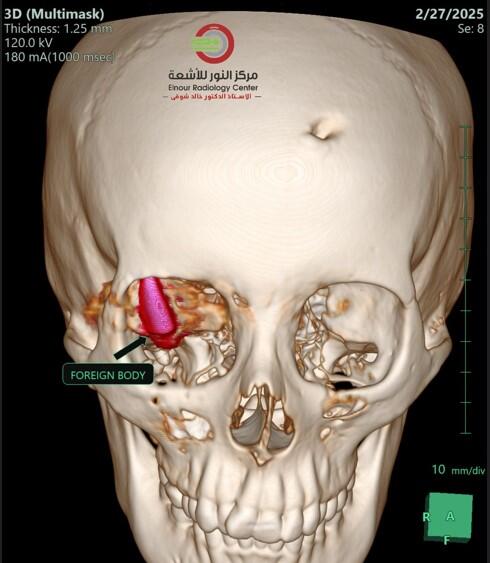

Three teams — ophthalmology, neurosurgery and radiology — worked together, debating the best approach to remove the bullet that had been lodged for months right next to al-Awady’s optic nerve.

“We ran several simulations to find the best route to avoid the optic nerve,” Dr. Mohamed Khaled Shawky, of the Al Nour Radiology Center, told CBS News. He helped guide the surgery remotely via a video link from his workstation at the separate facility.

“The bullet landed in the best possible place for the patient, but the worst place for a medical team,” Shawky told CBS News. “Had it moved a millimeter in any direction, it would have caused great damage.”

The doctors agreed the best option was to try to reach the bullet by entering through al-Awady’s eye socket, to avoid damaging her brain.